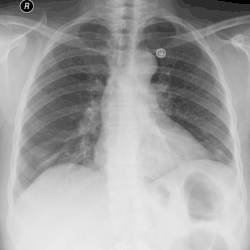

Для хронической эмпиемы характерно формирование симптома барабанных палочек. Отмечается укорочение перкуторного звука и ослабление везикулярного дыхания с поражённой стороны. Для диагностики используется подсчёт лейкограммы, рентгенография и компьютерная томография грудной клетки, ультразвуковое исследование[2].